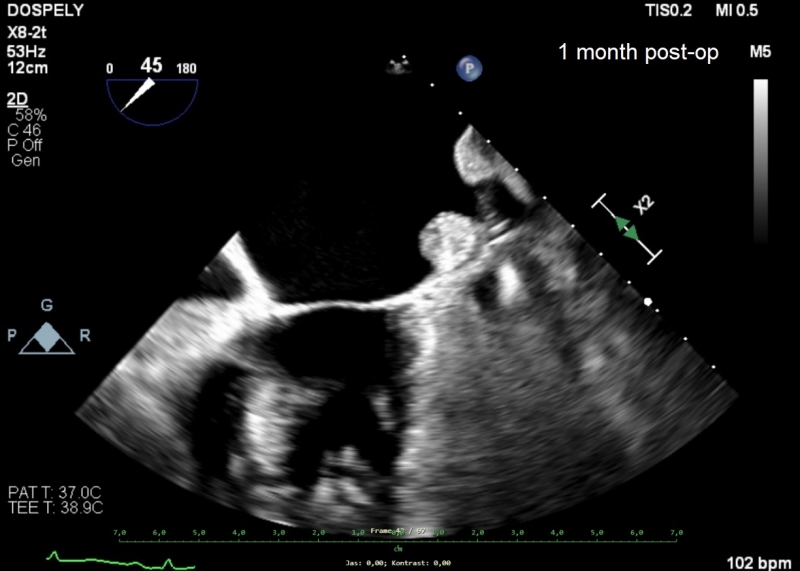

Pacienty následně sledujeme 1 rok. U všech pacientů pozorujeme postupnou regresi velikosti rezidua LAA, bez interference s okolními strukturami srdce. U jedné pacientky se složitější anatomií pozorujeme leak 5 mm. Nepozorovali jsme žádný trombus.